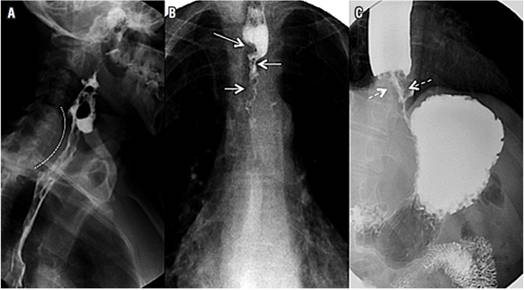

Disfagia cardiovascular

La disfagia cardiovascular hace referencia a múltiples enfermedades de naturaleza cardiovascular que causan compresión esofágica y disfagia secundaria; estas se pueden dividir en congénitas (doble arco aórtico, arco aórtico derecho, arco aórtico cervical, divertículo de Kommerell, arteria subclavia aberrante, arteria pulmonar en cincha, ligamento arterioso), adquiridas (disección aórtica, escoliosis, crecimiento de la aurícula izquierda) o iatrogénicas (fistula aortoesofágica, disfagia posoperatoria) 21,22.

El crecimiento de la aurícula izquierda secundario a enfermedades congénitas o adquiridas y asociado con estenosis mitral puede causar compresión esofágica con disfagia secundaria; esta constituye un diagnóstico diferencial en el estudio de la disfagia. Cuando el crecimiento de la aurícula es secundario a una valvulopatía mitral reumática y a parálisis del nervio laríngeo recurrente izquierdo, se conoce como síndrome de Ortner o disfagia cardiovocal21-23 (Figura 8).